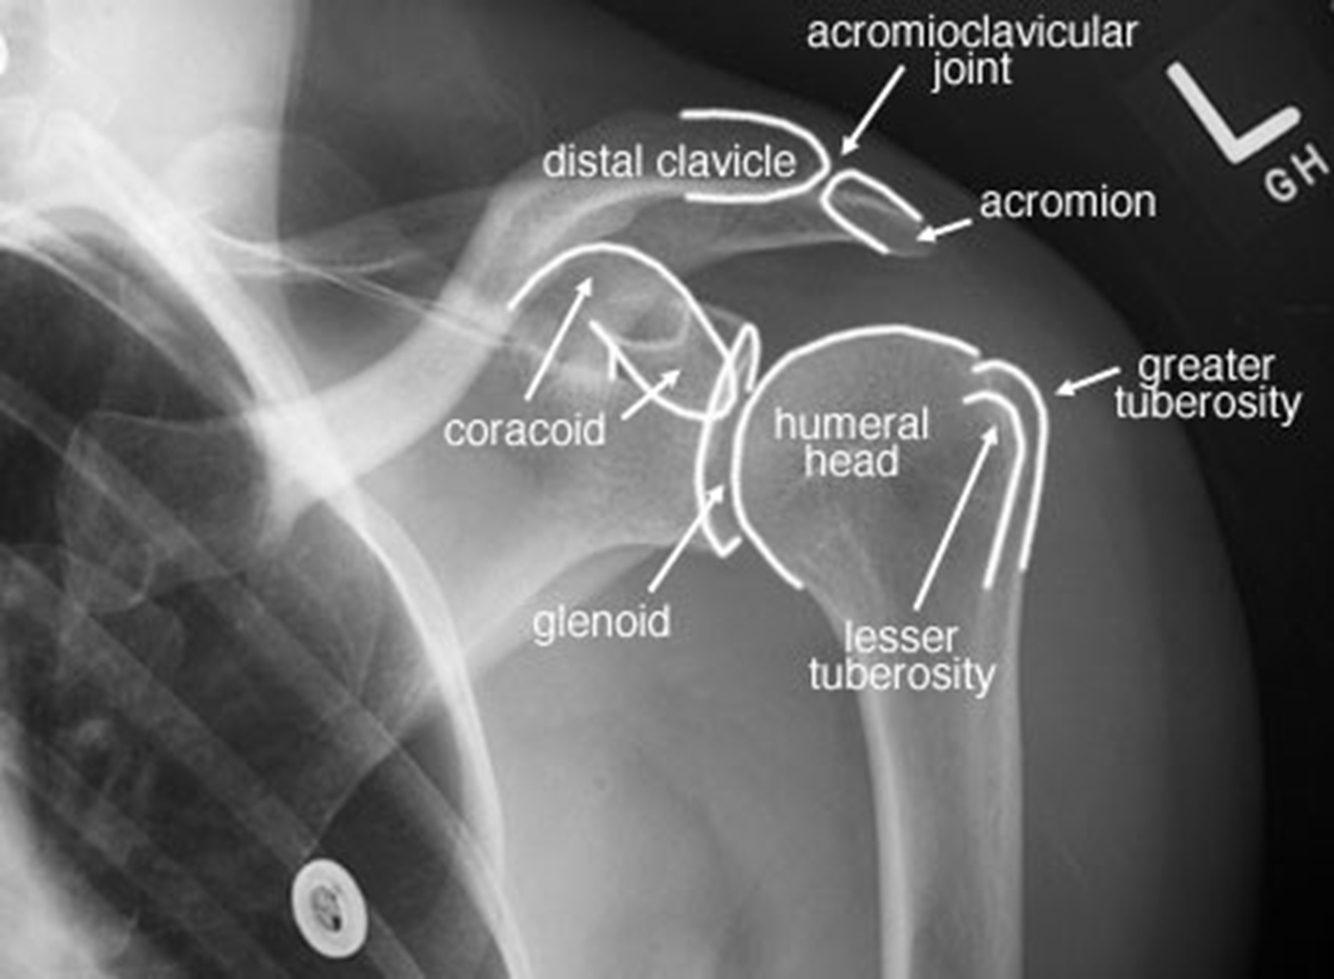

Review this radiograph of the shoulder.

27

Yet another radiograph. Knock yourself out